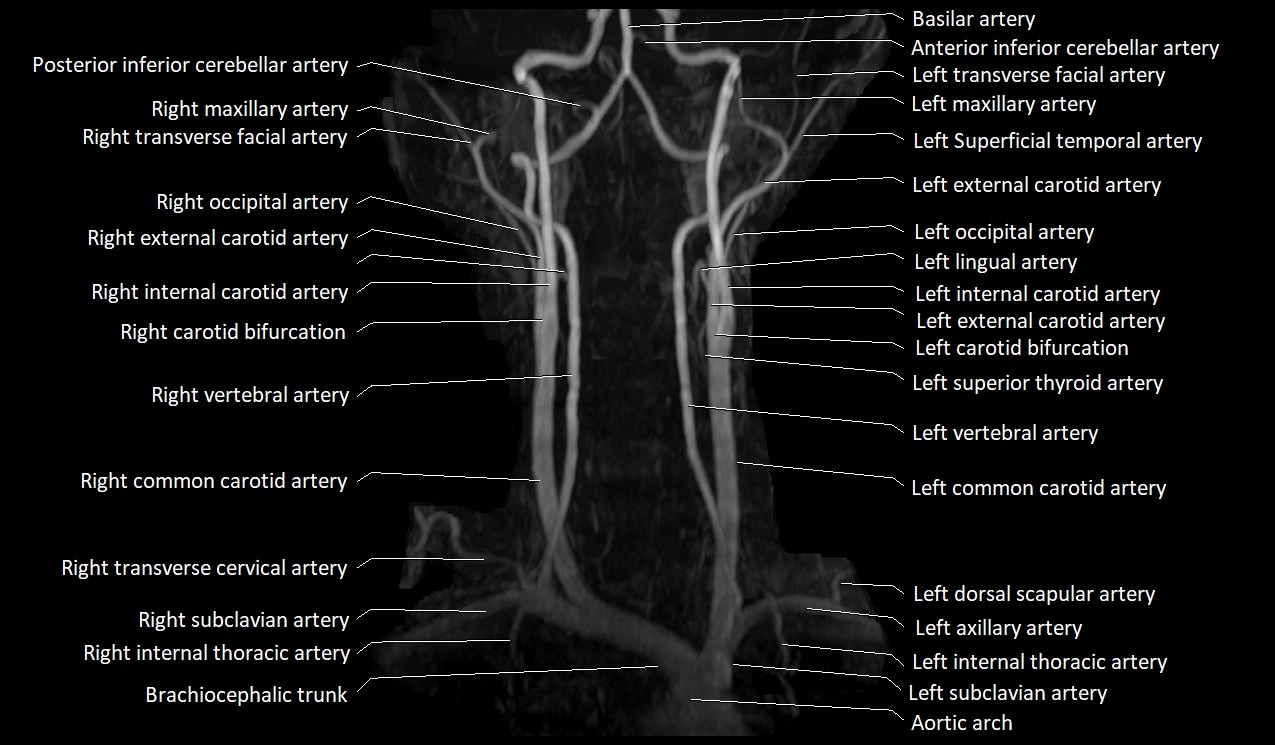

CT Appearance:

• Appears as a small, thin-walled, contrast-enhancing vein in the anterior neck

• Best visualized in the lower neck just lateral to the midline

• Non-contrast CT: difficult to differentiate from surrounding soft tissue, may appear as a hypoattenuating tubular structure

CTA (CT Angiography):

• Enhances brightly with intravenous contrast

• Easily visualized on arterial and especially venous phase images

• Shows continuity with external jugular vein or subclavian vein

CT image

image